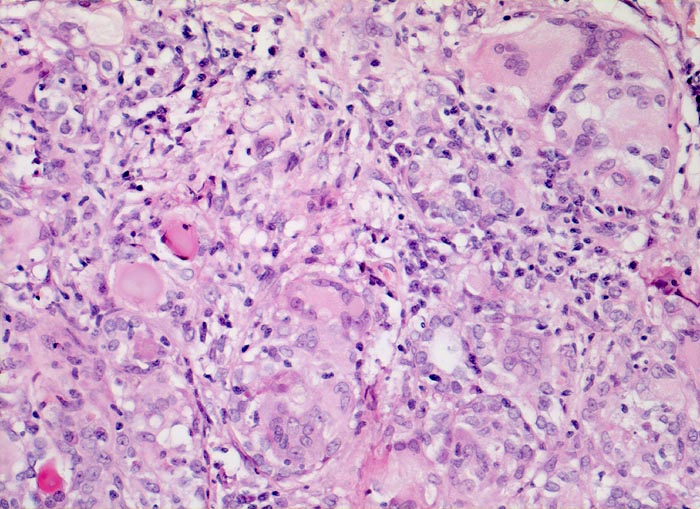

subakute Thyreoiditis de Quervain

Entzündung / Reparatur

Schilddrüse

Endokrinium

Granulomatöse Entzündung aus Riesenzellen und Lymphozyten. Dazwischen teilweise zugrundegegangene Follikel.

Euthyreose und kalte Knoten in beiden Schilddrüsenlappen.

Histologie

200